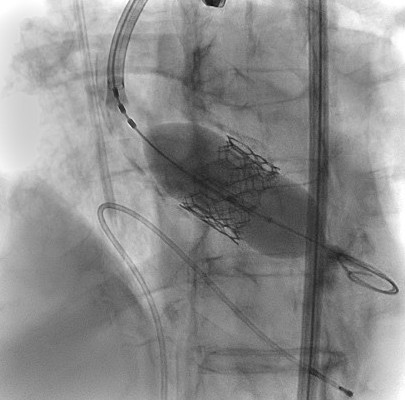

Cum funcționează: O valvă TAVI nouă este introdusă prin intermediul unui cateter și implantată în interiorul valvei originale deteriorate.

În această procedură, o a doua valvă TAVI este plasată în interiorul primei pentru a rezolva disfuncția valvulară. Este o opțiune de tratament în creștere, deoarece pacienții TAVI sunt adesea tineri și au o durată de viață care o depăseste pe cea a protezelor biologice, ceea ce duce la o nevoie crescută de reintervenție.